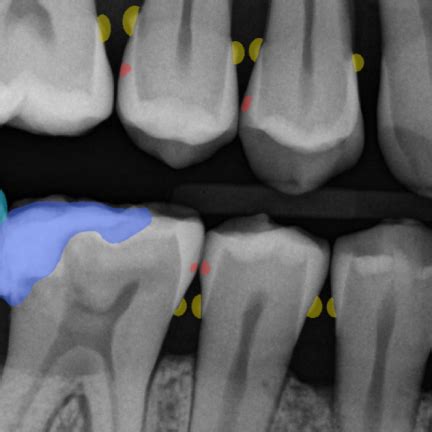

Alright, so how do we actually find these pesky thoracic spurs ? Enter the X-ray, your trusty medical sidekick. An X-ray is a type of imaging test that uses a small amount of radiation to create pictures of the inside of your body, in this case, your thoracic spine. It’s a quick and painless procedure that can reveal a lot about the condition of your bones and joints. When it comes to thoracic spine bone spurs , X-rays are usually the first step in diagnosing the problem. The images can clearly show the presence of these bony growths, their size, and their location relative to your vertebrae and other structures in your spine. It’s like a snapshot of your spine, allowing doctors to identify any abnormalities.

So, when you see those X-ray images, what are you looking for? Well, thoracic spine spurs will appear as small, bony protrusions along the edges of your vertebrae. They might look like tiny spikes or irregular bumps. The radiologist will also be looking at the overall alignment of your spine, the spaces between your vertebrae, and any signs of other conditions like osteoarthritis or degenerative disc disease. They’ll assess the size, shape, and location of the spurs to determine their potential impact on your health. However, an X-ray can only show the bone structure and not the soft tissues like muscles, ligaments, and nerves. If your doctor suspects nerve compression or other soft tissue issues, they might recommend additional imaging tests, such as an MRI or CT scan.